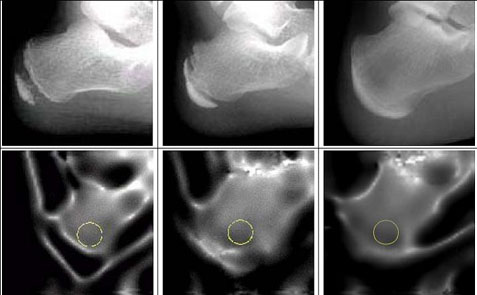

기존의 초음파 방식의 경우 고정점 방식을 이용하였기 때문에 피검자의 발의 모양이나 크기에 따른 오차를 보정할 방법이 없었기 때문에 이로 인한 검사 결과의 오차가 매우 컸으며, 초음파 스캐닝을 통해서 얻어진 결과를 이진화 방법을 통해서 정확한 종골의 영상을 얻어낸 것은 본 검사방법이 가지는 장점이라 할 수 있다. 또한, 같은 원리로 골피질부위와 성장판 부위의 밀도차를 이용하여 성장판의 개폐 여부를 확인하는 것이 가능하고 그 결과는 방사선을 이용한 검사 결과와 큰 상관관계를 보이고 있다.

성장클리닉에서 성장판 검사 및 골연령의 평가는 가장 중요한 진단 및 평가의 과정에 해당되는데, 본 검사는 다양한 형태의 종골 영상을 통해서 성장판 상태의 평가를 가능하게 하고, 골밀도의 변화를 토대로 골연령의 추측도 가능하다.

다만, 방사선 검사를 통한 영상에 비해서는 선명도가 떨어지고 골밀도만으로 골연령을 추정하는 것은 한계가 있기 때문에 일차적인 Screening용으로 적합할 것으로 여겨진다.